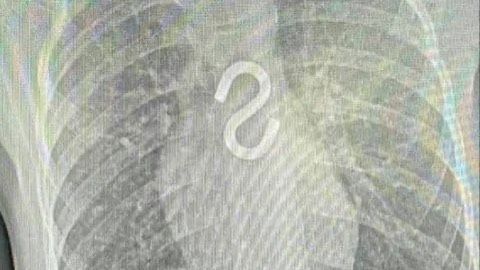

Иркутские врачи спасли двоих детей, которые проглотили строительный крючок и гвоздь.

Восьмилетнего мальчика в Ивано-Матрёнинскую больницу привезли родители. На рентгене медики увидели инородное тело в пищеводе— металлический крюк. Удалили под наркозом. Сейчас ребёнок в порядке — под наблюдением в отделении хирургии.

Вторым пациентом была трёхлетняя девочка: держала во рту гвоздик и случайно проглотила. На снимке его нашли в желудке, но во время операции оказалось, что острая часть уже стоит при входе в двенадцатиперстную кишку — быстро схватили зажимом и аккуратно вытащили.